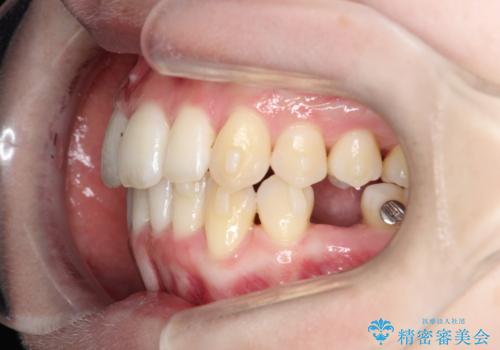

【インビザライン】 前歯の反対咬合を治したい

左下5番は先天性欠損のため乳歯は抜歯しインプラントにて欠損補綴しています。